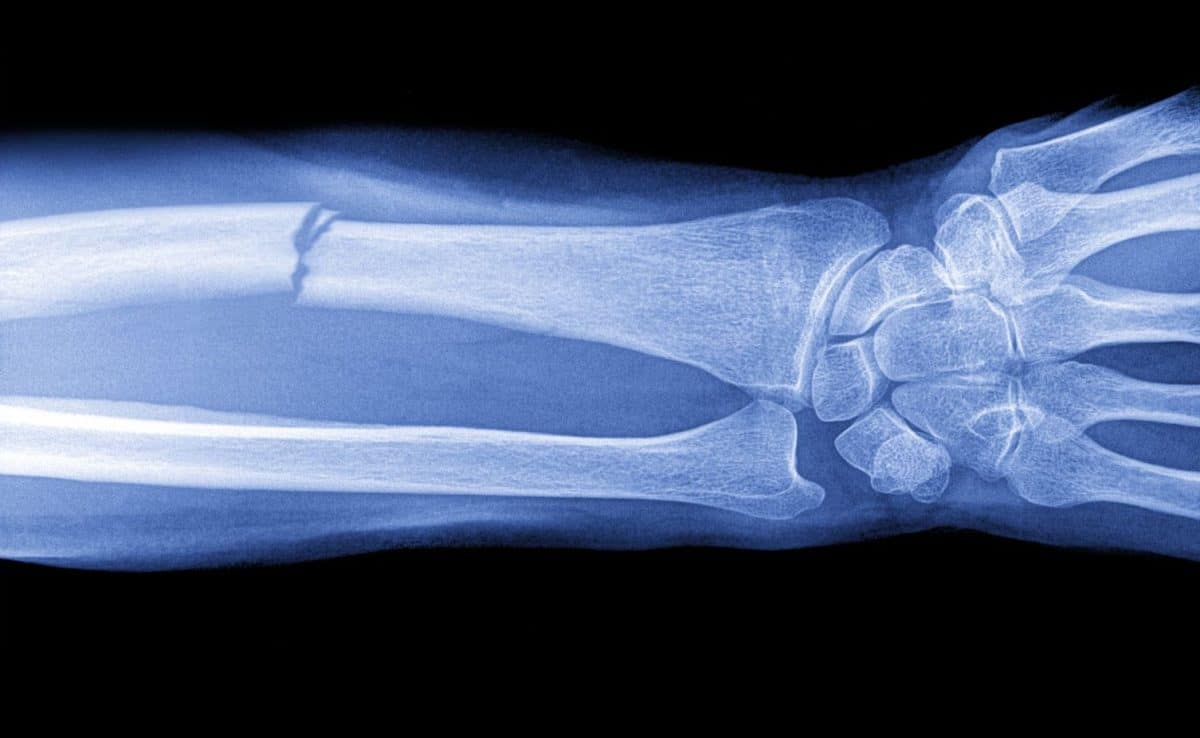

Ежегодно люди по всему миру сталкиваются с необходимостью восстановления после тяжелых травм, операций и возрастных изменений. Наибольшие трудности возникают при лечении масштабных повреждений костей, когда собственных ресурсов организма для заживления уже недостаточно. Существующие хирургические методики, в том числе аутопластика (пересадка собственных тканей пациента), не только требуют длительного восстановления, но и создают дополнительные медицинские риски. Ученые Пермского Политеха создали компьютерную модель, чтобы выявить оптимальные условия для регенерации костной ткани. Полученные результаты дают возможность проектировать структуру имплантатов, которая обеспечит максимально быстрое и качественное восстановление при серьезных повреждениях.

Костные дефекты представляют собой масштабную медико-социальную проблему. По данным ВОЗ, в среднем 1,71 миллиарда человек в мире страдают от нарушений и болезней костно-мышечной системы, требующих хирургического вмешательства. Рост травматизма, онкологических заболеваний и возрастного естественного старения создает устойчивую тенденцию к увеличению числа пациентов с подобными проблемами.

Природа предусмотрела механизмы регенерации костной ткани, но они эффективны лишь при незначительных повреждениях. Критический размер дефекта, превышающий два-три сантиметра, становится непреодолимым препятствием для естественного заживления. Организм не может самостоятельно восстановить обширные повреждения. Из-за этого вместо костной ткани формируется рубцовая, возникает ложный сустав, либо дефект не устраняется.